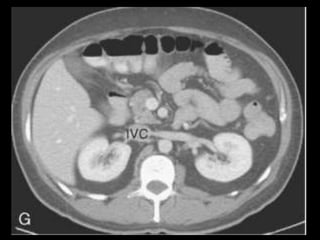

Coleções líquidas agudas

Ocorrem em cerca de 40% dos casos;

Podem ser em torno da glândula ou extra-

pancreático;

Carecem de cápsula e são confinadas ao espaço

anatômico onde se encontram;

Podem dissecar para outros locais: mediastino,

pararrenal posterior, órgãos sólidos ou parede de

alça intestinal.

Coleções líquidas agudas- TC

Hipodensas

Mal definidas

Sem cápsula ou parede reconhecível

Resolução espontânea em 50% dos casos;

Complicações: dor, infecção secundária e

hemorragia;

São passíveis de drenagem percutânea caso não

regridam ou se tornem infectadas.